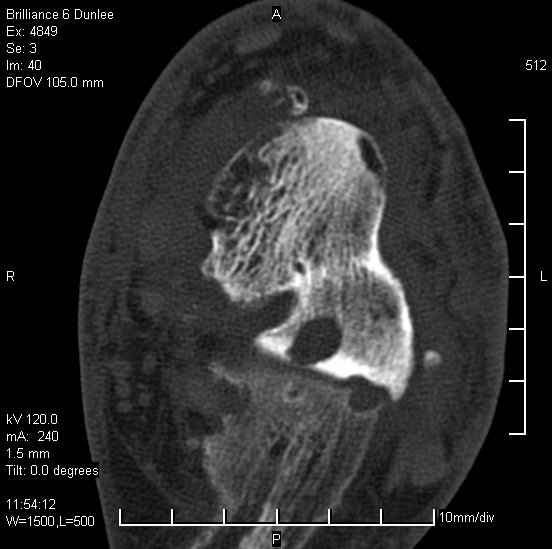

На лечении находится пациент 35 лет. Травма в сентябре 2008 г.- открытый вывих таранной кости

В день травмы ПХО, вправление вывиха, трансартикулярная фиксация. Рана зажила первично. С января нагрузка на конечность. С конца апреля- болевой синдром. На рентгенограммах и КТ признаки ас. некроза таранной кости, артроз подтаранного и голеностопного суставов.

У больного тотальный ас. некрох блока таранной кости, заинтересованы голеностопный и подтараный суставы. Эндопротезирование маловероятно на некротизированную кость. Изолированный подтаранный артродез таран не спасет.При артродезе всю некротизированную кость придется убрать.А далее замещение либо за счет большеберцовой кости, или удлинение на регенерате.